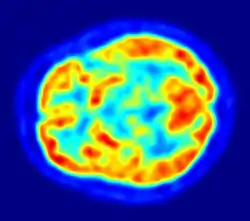

Vue axiale du cerveau par tomographie par émission de positons.

Les neurophysiologistes étudient les propriétés chimiques, pharmacologiques et électriques du cerveau. Leurs principaux outils sont les drogues et les dispositifs d'enregistrement. Des milliers de drogues expérimentalement développées affectent le système nerveux, plusieurs le font de manière très spécifique. L'enregistrement de l'activité cérébrale peut se faire par l'utilisation d'électrodes, soit collées au crâne comme dans le cas d'électro-encéphalographie, soit implantées à l'intérieur du cerveau pour des enregistrements extracellulaires, qui peuvent détecter les potentiels d'action générés par des neurones individuels. Comme le cerveau ne contient pas de nocicepteurs, il est possible d'utiliser ces techniques sur un animal éveillé sans causer de douleur. Il est aussi possible d'étudier l'activité cérébrale par un examen non invasif en utilisant des techniques d'imagerie fonctionnelle comme l'IRM. Ainsi la tomographie à émission de positons met en évidence qu'en l'absence de toute focalisation particulière de l'attention, l'activité du cerveau (activité intrinsèque du réseau du mode par défaut, nommée « énergie sombre du cerveau » par analogie à l'énergie sombre du cosmos[82] et qui consiste en des vagues d'ondes électriques lentes) correspond à une dépense de 60 à 80 % de toute l'énergie consommée par le cerveau, soit une énergie 20 fois supérieure à celle consommée par le cerveau lorsqu'il réagit consciemment, la réalisation d'une tâche particulière (activité consciente moins fréquente que l'activité inconsciente) exige une énergie qui n'excède pas 5 % de celle consommée par l'activité de fond[83].